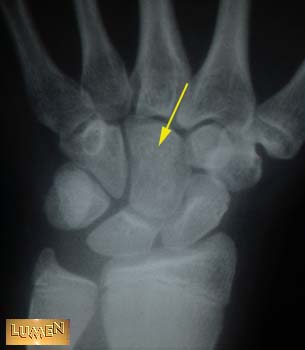

17. Identify Bone.

Capitate.